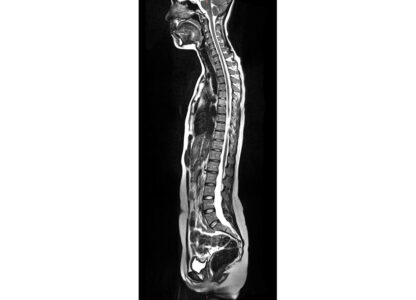

This photo provided by Prenuvo in July 2024 shows an MRI scanner. Magnetic resonance imaging uses magnetic fields to produce detailed images of organs, bones and other structures inside the body. Unlike many other types of scans, MRIs don't use radiation. (Prenuvo via AP)

MRI stands for magnetic resonance imaging. It’s a type of medical scan that uses magnetic fields to produce detailed images of organs, bones and other structures inside the body. Unlike many other types of scans, MRIs don’t use radiation.

Doctors will order an MRI to help diagnose cancer, brain injuries, damaged blood vessels and other medical conditions. Full-body scans can take an hour or more, with patients lying motionless inside a cylindrical tube.